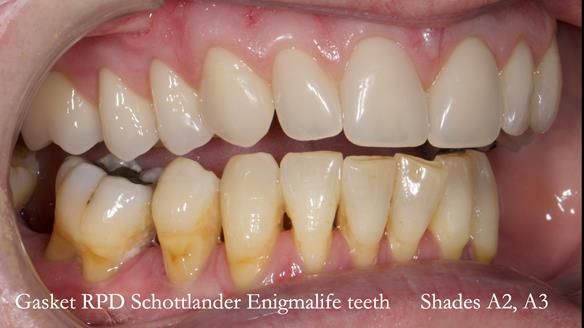

Welcome to my Newsletter 58, where I show the making and fitting of an upper gasket partial denture for Zoe (52 year old woman). This issue provides a comprehensive overview of the entire protocol workflow for this superbly retained denture.

Zoe was referred to me for specialist prosthodontics by her general dentist, after unsuccessful attempts to provide a denture because of fractures, looseness and discomfort.

The detailed clinical situation and treatment process are outlined below, with clinical work provided by me and technical work by Rowan Garstang. The treatment spanned five visits for denture fitting and one review.